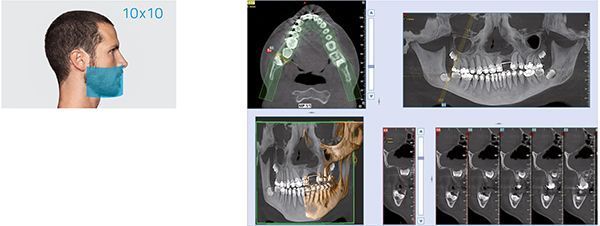

Изображения высокого качества, которые соответствуют широкому диапазону задач клинической диагностики, все в одном компактном устройстве. GO 2D/3D CEPH – гибкая платформа, готовая к опциональной интеграции телерентгенографического модуля в 2D или 3D конфигурации. Платформа, способная создавать изображения в высоком разрешении, выводит здоровье пациента в приоритет благодаря протоколам низкого облучения и эксклюзивной технологии SafeBeam, которая позволяет подбирать дозу под конкретную диагностическую задачу и размер сканируемой анатомической области. Отличная эргономика и система адаптивного выравнивания обеспечивают правильное положение пациента и идеальную фокусировку для четкого подробного изображения. Виртуальная панель управления сопровождает пользователя на каждой стадии осмотра. NNT – технологически передовая программная платформа для управления, обработки, консультирования и распространения диагностических снимков.

Программное обеспечение NewTom NNT предлагает все функции, необходимые для выполнения, обработки, вывода на экран и передачи 2D и 3D результатов обследования. NNT также предоставляет различные режимы и функции приложения, специально предназначенные, чтобы планировать лучшее лечение в области имплантологии, эндодонтии, пародонтологии и рентгенографии, а также в челюстно-лицевой хирургии.

NewTom GO генерирует выдающиеся объемные изображения и для каждого FOV в диапазоне от 6х6 до 10х10 см. Выбор из 3 протоколов позволяет адаптировать требуемую дозу рентгеновского излучения к конкретным потребностям: от очень низкой для быстрого сканирования, необходимого при последующих хирургических проверках, до регулярной для планирования лечения, до очень высокого уровня детализации для анализа микроструктур.Минимальная доза, максимальное диагностическое качество

NewTom GO создаёт выдающиеся объемные изображения для каждого поля обзора, от 6*6 до 10*10 см. Выбор из 3 протоколов позволяет устанавливать дозу излучения, требуемую для конкретной задачи: от очень низкой для быстрого сканирования при хирургическом наблюдении, средней для планирования лечения, до очень высокого уровня детализации для анализа микроструктур.